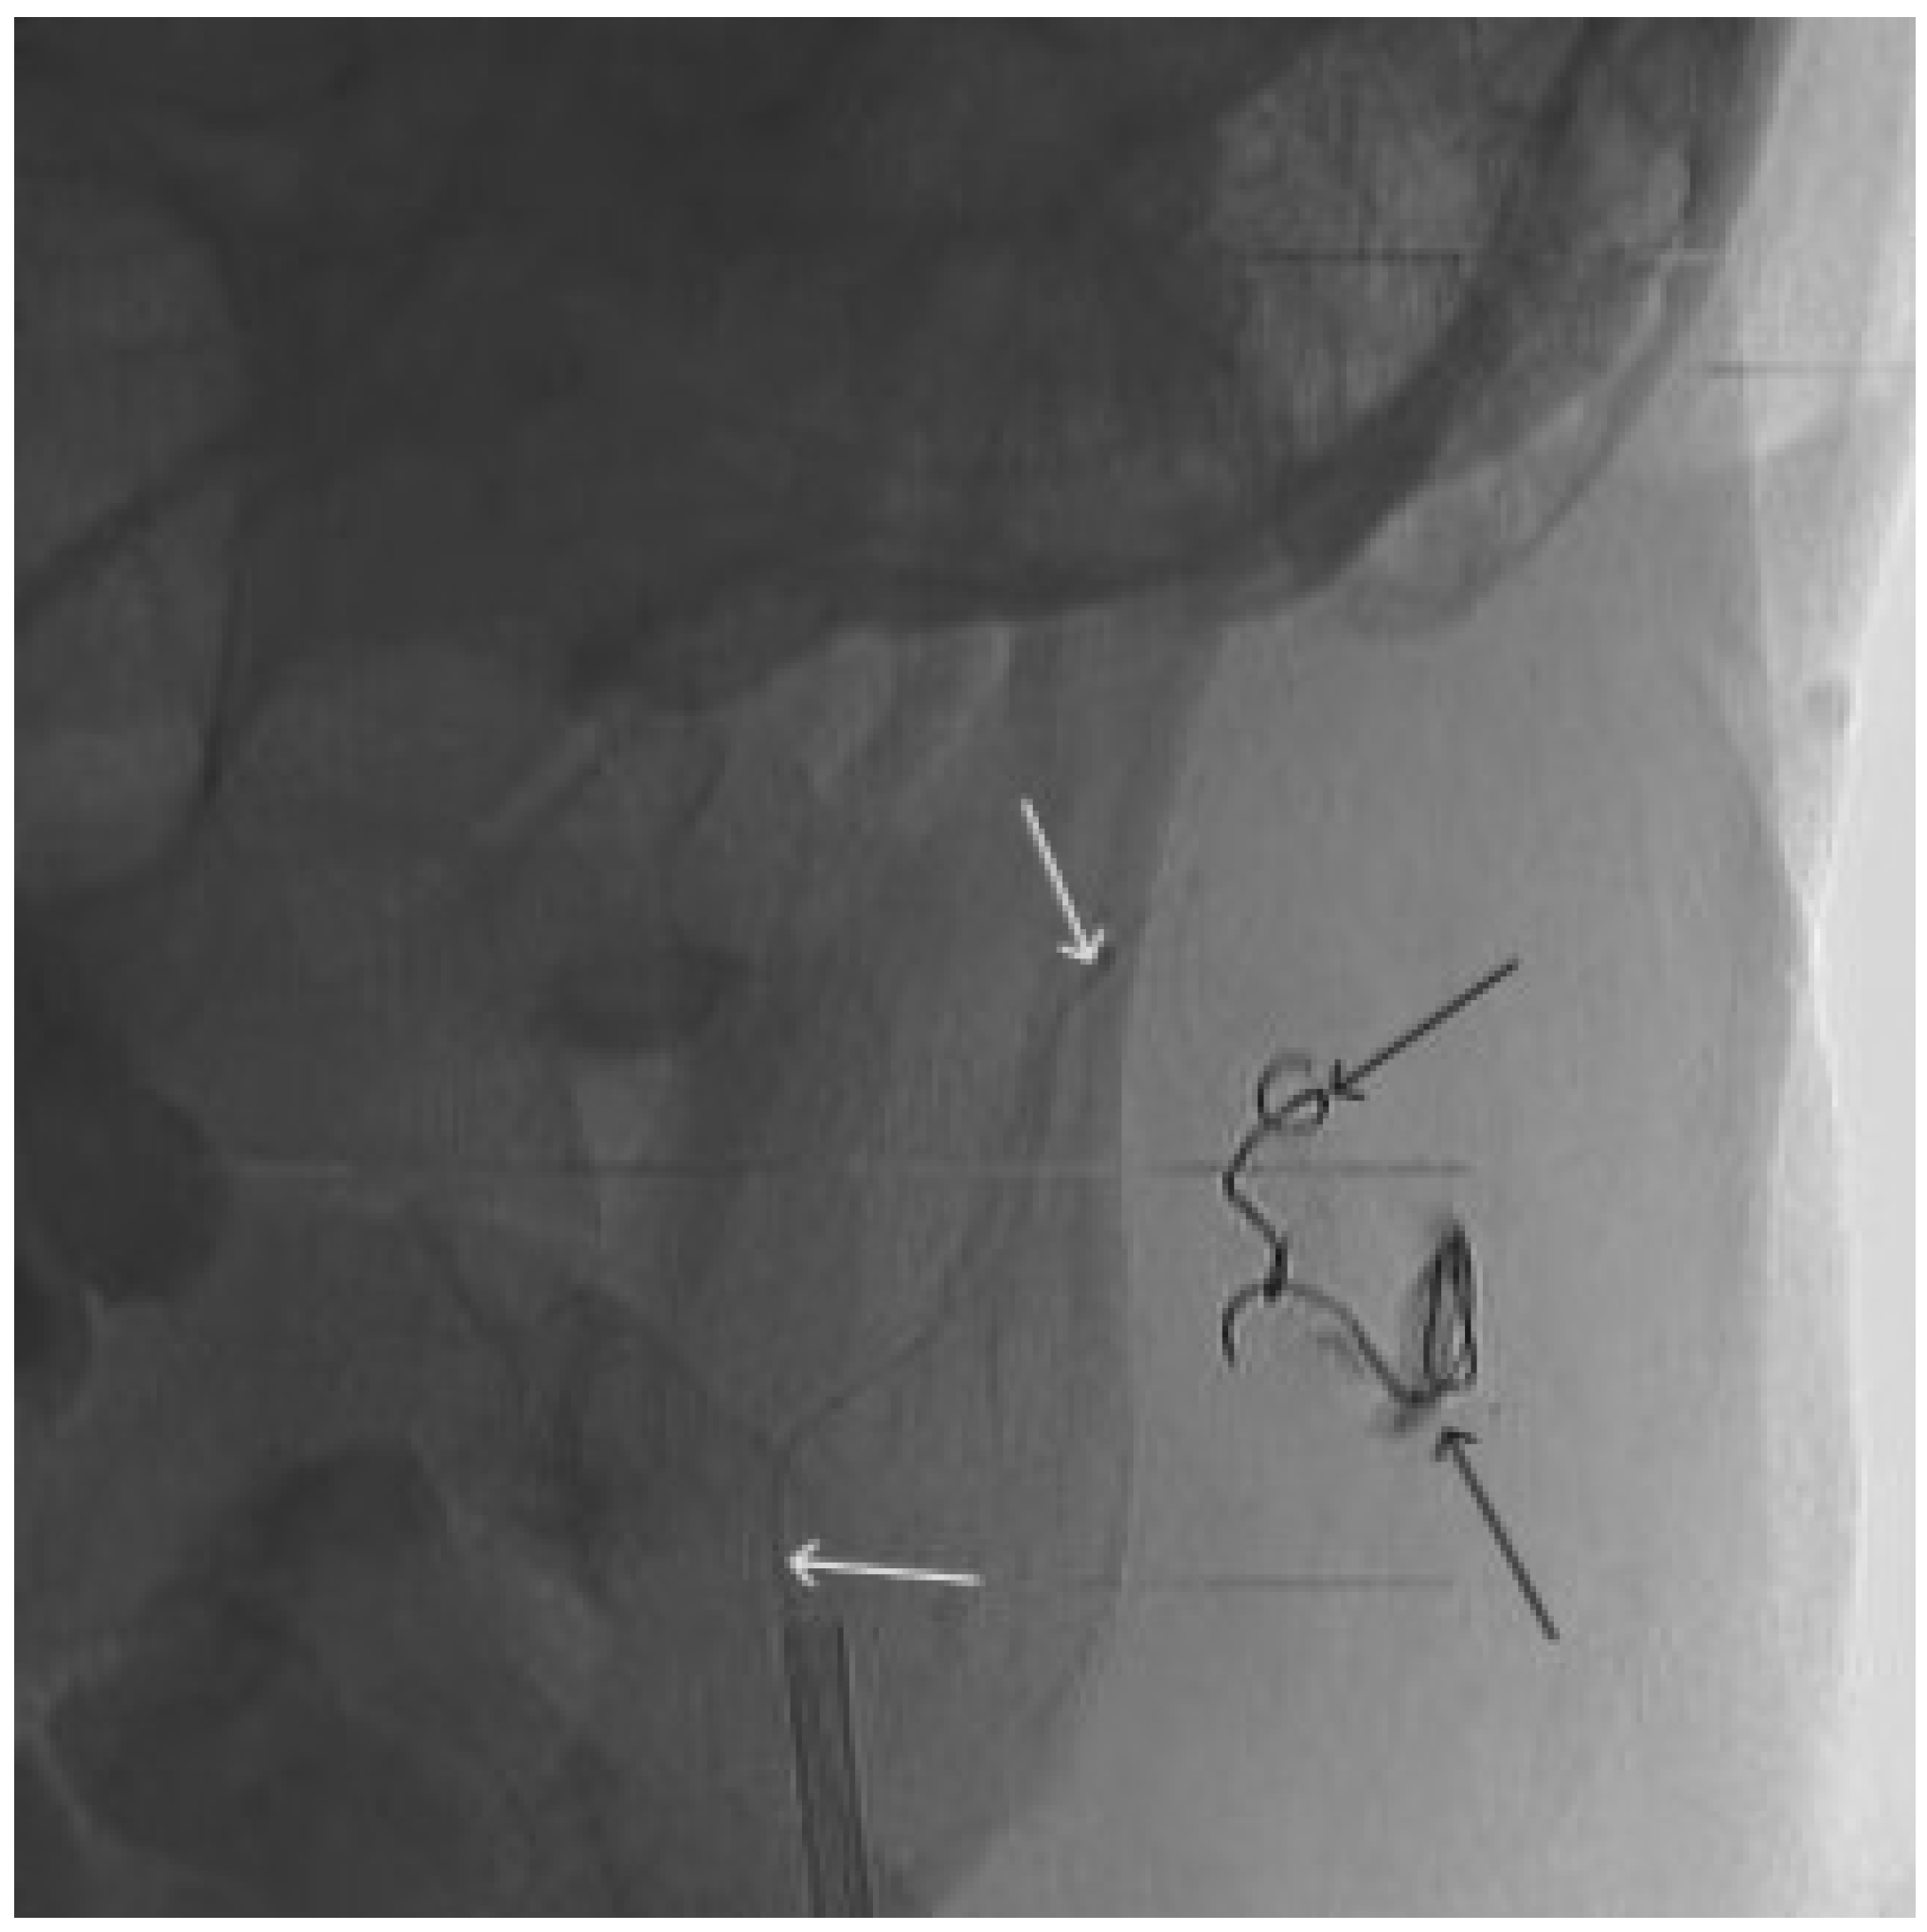

Figure 9. X-ray, direct projection (the white arrow indicates a microcatheter in the left external carotid artery, the black arrows indicate a complex of microcoils from the previous stage of embolization.